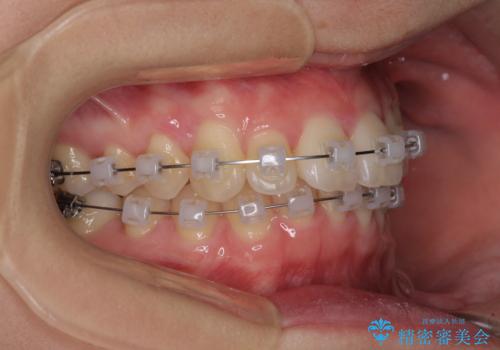

- クリアブラケット

ぱっと見はインビザラインによる矯正治療も可能と思われましたが、歯根が最も長い犬歯がクロスバイトになっており、インビザラインでは対応困難と判断され、ワイヤー装置にて矯正治療を行うこととしました。

クロスバイトになっている犬歯は、歯の移動に伴い装置を張り替えていくことで対応することとしました。

クロスバイト改善中には歯髄壊死を起こすリスクがあるため、神経に問題がないか確認しながら治療を進めて行く必要があります。

思っていたよりも早くクロスバイトは改善され、歯髄壊死に至ることなく、無事に治療を終えることができました。